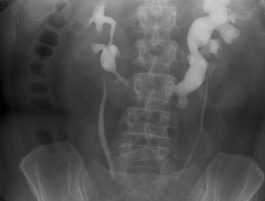

Внутривенная урография. Подковообразная левая почка.